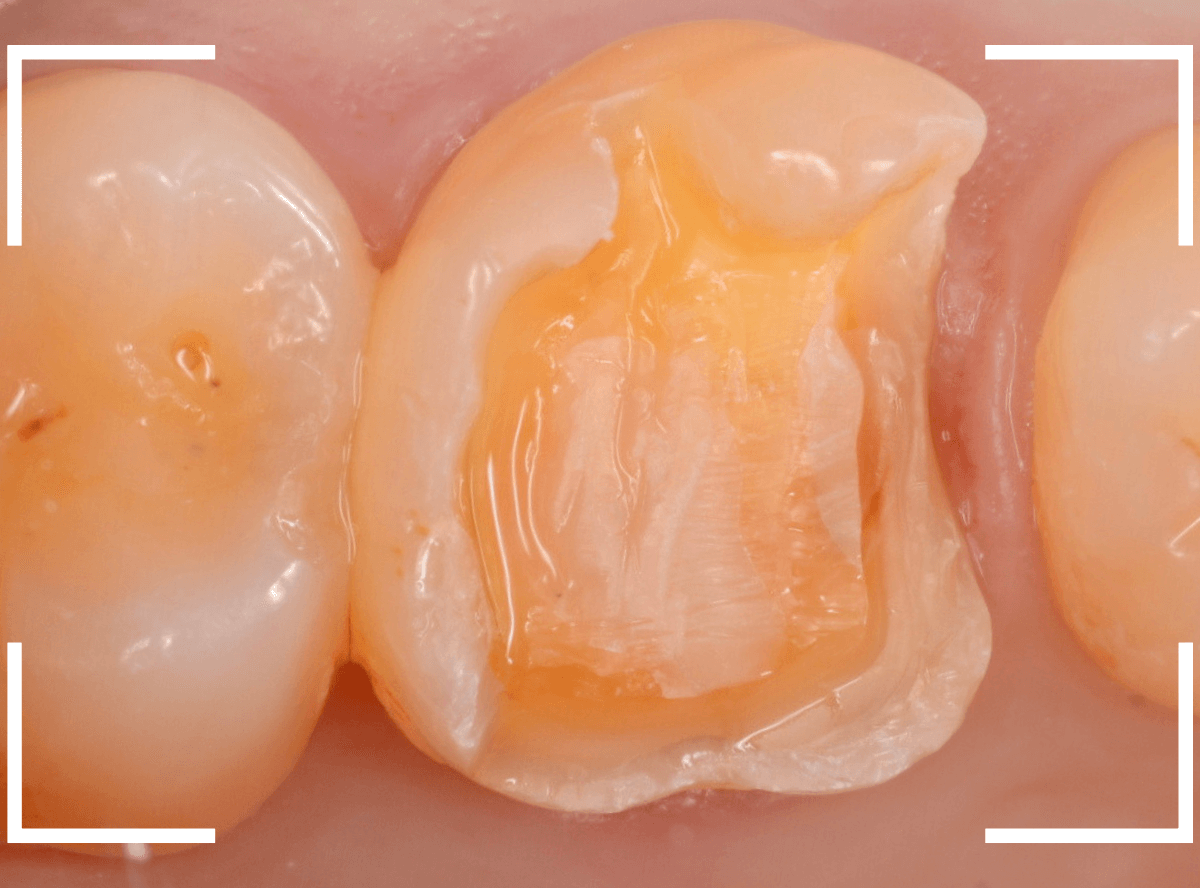

セラミックが精密にsetできるように、歯をトリミングします。

模型上で精密に製作します。